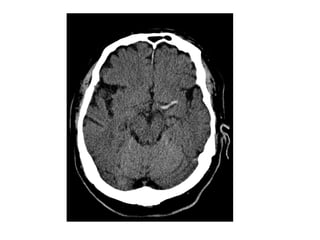

CT without contrast , cerebral venous thrombosis

CT without contrast , cerebral venous sinus thrombosis